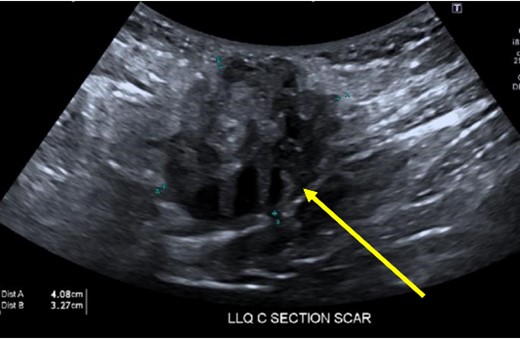

A 38-year-old female with past medical history of hypertension, migraine headaches, and anemia as well as past surgical history of two Cesarean sections presented to our general surgery clinic with a painful abdominal mass at the left lateral aspect of her Pfannenstiel incision. She reported that her most recent Cesarean section was 4 years ago with recurrent pain over the incision for about 2 years. Of note, 2 years prior to presentation at our clinic, she was seen by a general surgeon for similar symptoms and was found to have two subcutaneous nodules at the lateral edge of the Pfannenstiel scar. Ultrasound of the region at that time showed two hypoechoic, nonvascular, and non-fluid-filled subcutaneous nodules suggestive of suture granulomas (Fig. 1). Since then, she had experienced intermittent discomfort. More recently, each month at the time of menstruation, she stated that the mass would enlarge and become more painful. After menstruation, the mass would decrease in size and the pain would recede. On this visit, ultrasound revealed a heterogeneous vascular soft tissue mass measuring 4.1 × 3.3 × 4.4 cm, suspicious for endometrioma in the setting of her clinical history (Fig. 2).

Heterogeneous, vascular nodule (arrow) measuring 4.1 × 3.3 × 4.4 cm, suggestive of endometrioma.